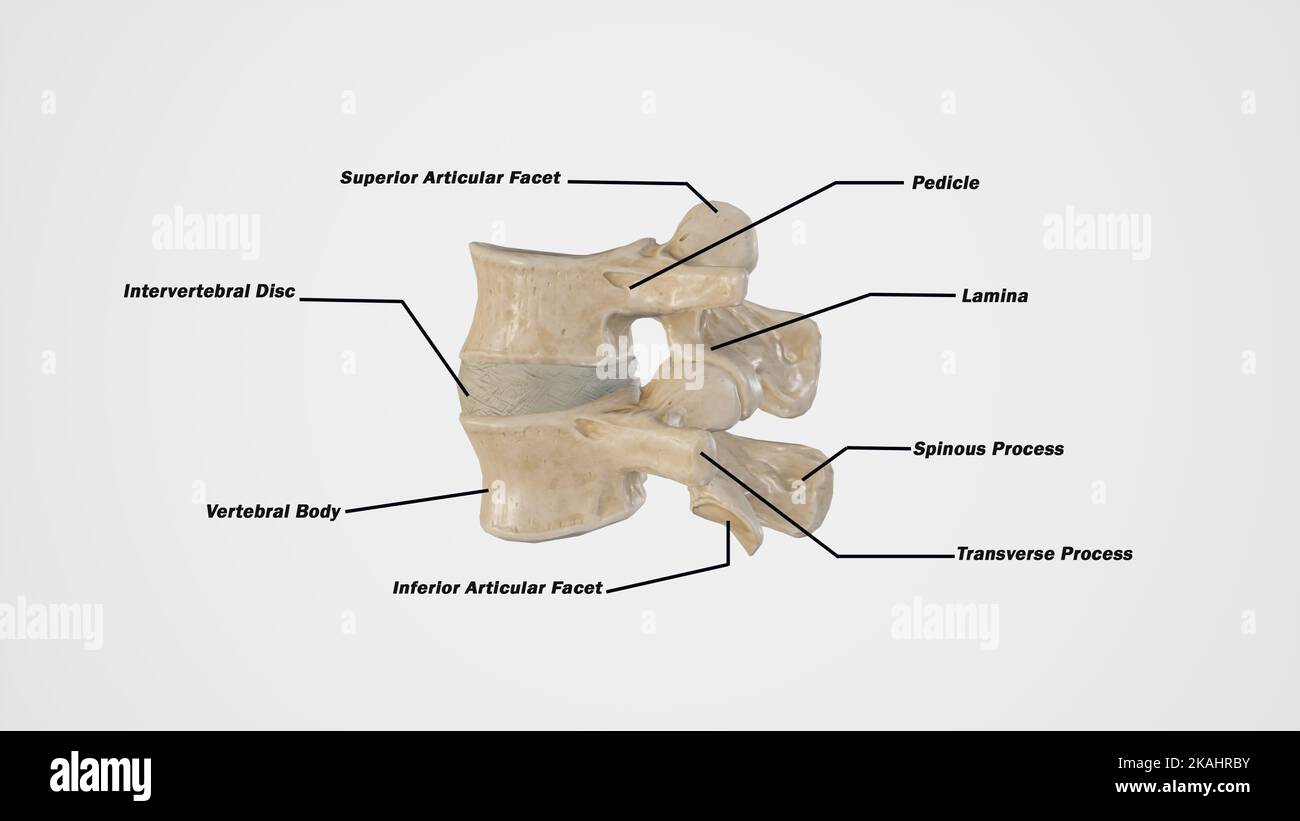

RMW9G8YY–Immagine di archivio da pagina 144 di Cunningham il libro di testo di anatomia (1914). Cunningham il libro di testo di anatomia cunninghamstextb00cunn Anno: 1914 ( le nervature. Ill sfaccettature sulla testa Xeck Xon-articolare parte del tubercolo parte articolare del tubercolo per processi trasversali delle vertebre Fig. 124.-quinta costola destra come visto da dietro. attrezzatura per esterni ed interni dei muscoli intercostali rispettivamente. Sul pavimento della scanalatura può essere visto anche le aperture dei canali per la trasmissione delle navi di nutrienti che sono orientati verso la estremità vertebrale della nervatura. La sezione anteriore o extremi sternale

RMPFYCG2–. Cunningham il libro di testo di anatomia. Anatomia. Parte articolare del tubercolo per processi trasversali delle vertebre Fig. 124.-quinta costola destra come visto da dietro. attrezzatura per esterni ed interni dei muscoli intercostali rispettivamente. Sul pavimento della scanalatura può essere visto anche le aperture dei canali per la trasmissione delle navi di nutrienti che sono orientati verso la estremità vertebrale della nervatura. La sezione anteriore o estremità sternale dell'albero, spesso leggermente ingrandita, visualizza un ovale allungata buca in cui la cartilagine costale è affondato. Nervature peculiare.-Il primo, il secondo, decimo e undicesimo di

RMMA6YGG–. Fisiologia elementare . Processo RANSVERSE ^SUP AR7IC.processo peduncolo Fig. 8.-decima vertebra dorsale, dall'alto. (Disegnata da D. Gunn.) nel caso di tali vertebre per cui le nervature sono allegate (dorsale vertebrse), ciascuno di questi processi trasversali porta una piccola faccetta articolare, per cui un simile aspetto sul corrispondente nervatura è applicato. Sui corpi di questi stessi vertebrse dorsale al di sopra e al di sotto di ogni lato vi è una metà sfaccettatura, che in ogni caso si congiunge con il suo prossimo nella vertebra più vicina per fare tutta una sfaccettatura, per l'articolazione con la testa della costola. In modo tale che ciascuna nervatura ha due punti di interesse

RMPFYCG4–. Cunningham il libro di testo di anatomia. Anatomia. Le nervature. Ill sfaccettature sulla testa Xeck Xon-articolare parte del tubercolo. Parte articolare del tubercolo per processi trasversali delle vertebre Fig. 124.-quinta costola destra come visto da dietro. attrezzatura per esterni ed interni dei muscoli intercostali rispettivamente. Sul pavimento della scanalatura può essere visto anche le aperture dei canali per la trasmissione delle navi di nutrienti che sono orientati verso la estremità vertebrale della nervatura. La sezione anteriore o estremità sternale dell'albero, spesso leggermente ingrandita, visualizza un ovale allungata abisso nel quale le carti costiera